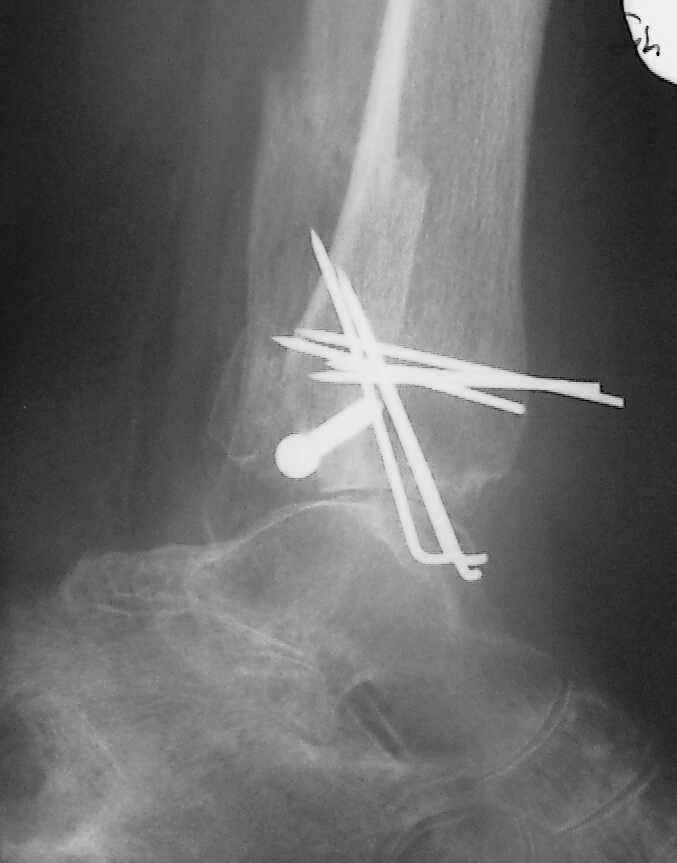

Больная 1936 г.,травма 15 ноября 2003,закрытый трехлодыжечный перелом г/стопного сустава, сахарный диабет.

При поступлении - закрытая репозиция, повторная в связи с большим отеком через неделю, подготовлена к остеосинтезу в первых числах декабря. Заживление без осложнений. Циркулярный гипс - 7 недель, снят,часть спиц удалено 20 февраля т.к.пальпировались под кожей, постепенная нагрузка, проблем нет до середины апреля когда появильсь боли с мед. стороны сустава и локалная гиперемия ( трактовалась как флеботромбоз). Повторное поступление 15 апреля - усиление болей,пов. температура, локально выраженная гиперемия.Локально выделений нет. На RTG - деструкция в области мед лодыжки и заднего края. Сахар крови умеренно повышен. Как трактовать проблему, какой диагноз и тактика лечения? Заранее спасибо, Владимир.